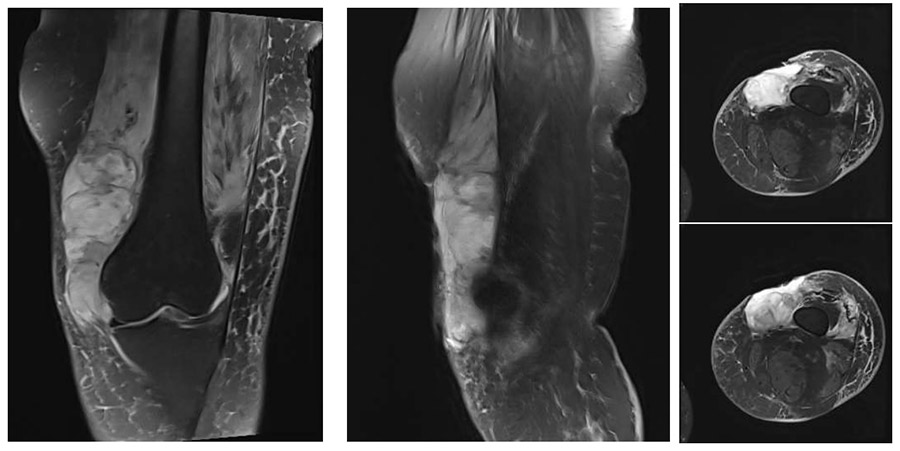

Ameliyat Öncesi: MR’da sol distal uyluk medialde femurun üzerine otrumuş olan düzensiz sınırlı çevreleyen ödemin eşlik ettiği heterojen kitle ve üzerinde cilt defekti görülmekte